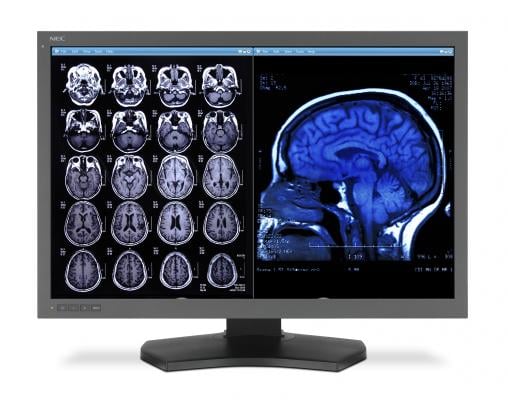

In use by a growing number of radiologists and neuroradiologists in the United States and Europe, Neuroreader analyzes magnetic resonance imaging (MRI) scans of patients' brains and benchmarks them against a U.S. Food & Drug Administration (FDA)-cleared database of healthy brain tissues in a matter of minutes. The software measures 45 specific structures within the brain.

When treating a patient with signs of neurodegenerative diseases, the physician simply uploads the MR image to the Brainreader server. Neuroreader then analyzes the MRI scan and delivers a report in less than five minutes, indicating which brain structures' volume are abnormal and to what extent. The software, which has an intuitive interface, produces an easily interpreted automated report.